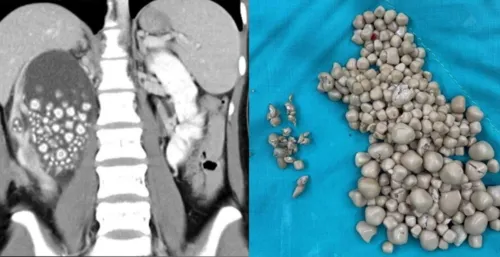

Uma jovem de 20 anos precisou passar por uma cirurgia de emergência para retirar mais de 300 pedras de um dos seus rins. De acordo com informações do Hospital de Chi Mei, em Taiwan, onde ela foi atendida, a mulher compareceu na instituição de saúde apresentando sintomas como febre e dores no quadril.

As maiores pedras entre as centenas retiradas do corpo da jovem tinham cerca de 2 centímetros de diâmetro. Apenas o rim esquerdo dela foi atingido. Foi feita uma nefrolitotripsia percutânea, procedimento considerado minimamente invasivo, em que as pedras são retiradas por um pequeno corte feito nas costas. A paciente recebeu alta poucos dias depois do procedimento.